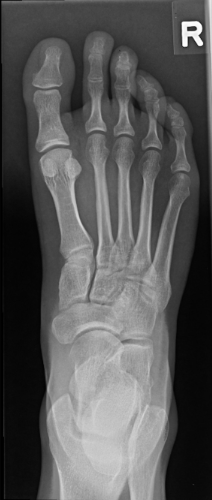

9

Q

correction

A

needs more cephalad angle

(TMTs are closed)